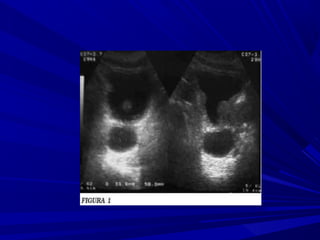

EVALUACIÓN ECOGRÁFICA

La evaluación de las glándulas adrenales

consiste en describir:

La posición,

La forma,

La ecogenicidad,

La arquitectura y

El tamaño de cada glándula adrenal.